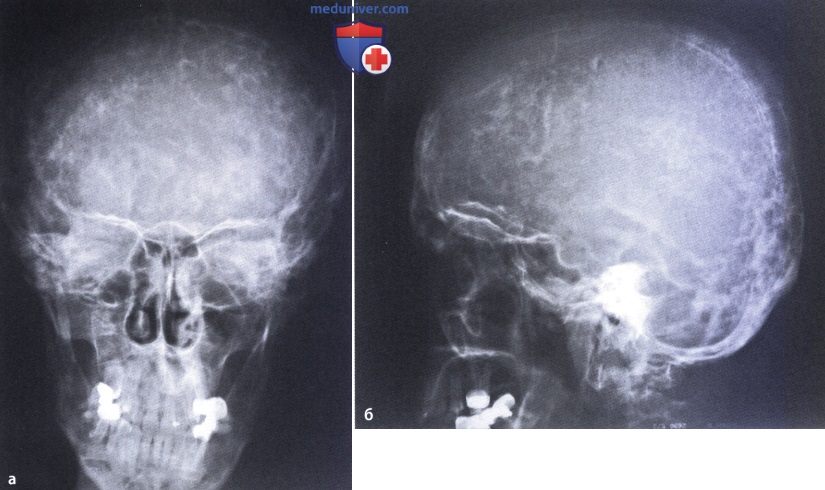

Рентгеновские снимки и визуализация болезни Педжета

Раздел: Мудрость в объективе